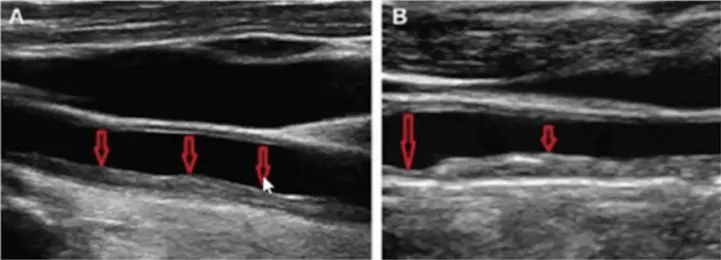

— Если человека ничего не беспокоит, рутинно назначать эхокардиографию, ЭКГ обычно избыточно. А вот УЗИ брахиоцефальных артерий (УЗДГ/дуплексное сканирование сосудов шеи. — Reminder) я после 40 лет назначаю всем. Там мы, в частности, измеряем толщину комплекса интима-медиа: в норме она должна быть меньше 1 мм.

— Это самый простой и быстрый способ оценить общую сосудистую картину. Эти артерии хорошо доступны ультразвуку, и считается, что если бляшка есть хотя бы в одном месте, то, скорее всего, атеросклеротический процесс затрагивает и другие сосудистые бассейны.